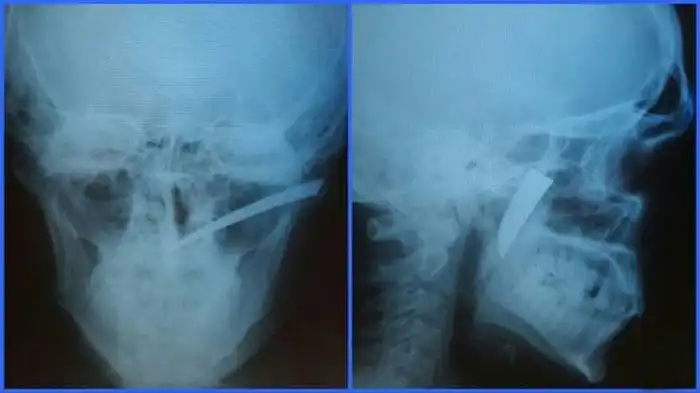

Нередко врачи вынуждены извлекать из тел людей самые необычные посторонние предметы, которые не должны были там находиться. В данном случае из мягкого нёба мужчины достали лезвие небольшого ножа, вошедшего под скуловой дугой во время драки. Случилось это за месяц до обращения за медицинской помощью, а беспокоиться пациент начал только потому, что нащупал нечто постороннее в нёбе.